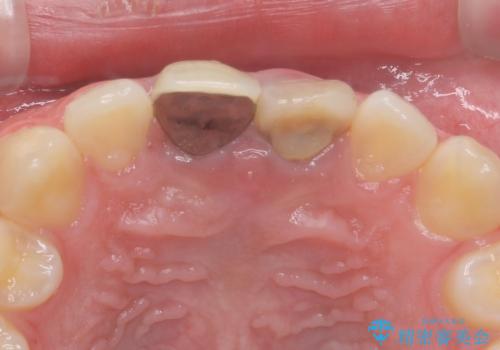

前歯の変色 神経のない歯の再治療

- 前歯の変色を気にして来院。

過去に神経の治療を行ったとのことでした。

特に右上の前歯の膿は大きくなって歯ぐきから排膿している状態でした。(フィステルといいます)

二本とも神経の治療のやり直し(再治療)を行ってからセラミックを入れています。